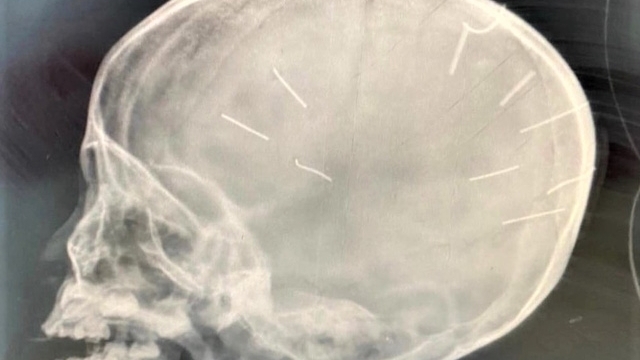

Đáng nói, khi khám nghiệm thi thể bé V.A, công an phát hiện nhiều dấu bầm tím nghi do bạo hành. Hàng xóm cũng đã phản ánh về những âm thanh la hét từ căn hộ chung cư được cho là của bé V.A và người trút đòn roi xuống em được cho là Trang.